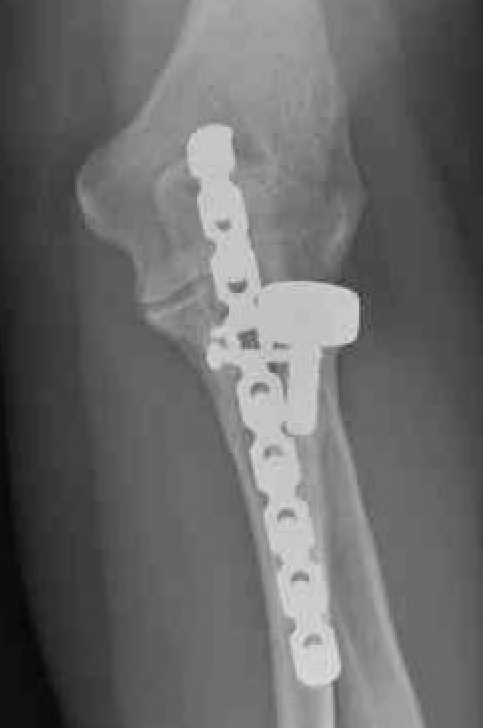

Olecranon plate + ORIF Type II coronoid process + radial head replacement

Olecranon plate with radial head replacement

Olecranon plate with radial head replacement + LCL repair

Olecranon plate + medial coronoid buttress plate + radial head replacement